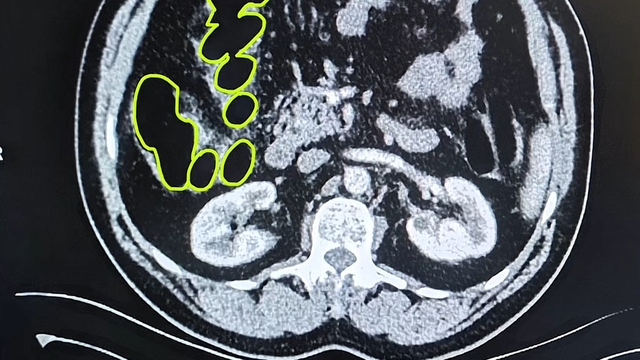

İl Jandarma Komutanlığı ekipleri, İran uyruklu A.O. (51), M.S. (37) ve P.S..'nin (28) ülkelerinden kente uyuşturucu getireceği bilgisine ulaştı. Şüpheliler Kocasinan ilçesi Himmetdede Mahallesi'nde taksi ile kente girmek istediği sırada durduruldu. Araçta yapılan aramada 15 gram esrar, 5 gram bonzai ve 117 adet uyuşturucu hap ele geçirildi. Gözaltına alınan 3 şüpheli muayene olmak üzere Kayseri Şehir Hastanesi'ne getirildi. Röntgen ve ultrason sonrası kontrollerde 3 şüphelinin midesinde uyuşturucu madde olduğu belirlendi. Şüphelilerin yuttukları uyuşturucuları kente sokmaya çalıştıkları tespit edildi. Kapsüller, sağlık ekibinin müdahalesiyle çıkarıldı. Taburcu edilen şüpheliler, İlçe Jandarma Komutanlığı'na götürüldü.